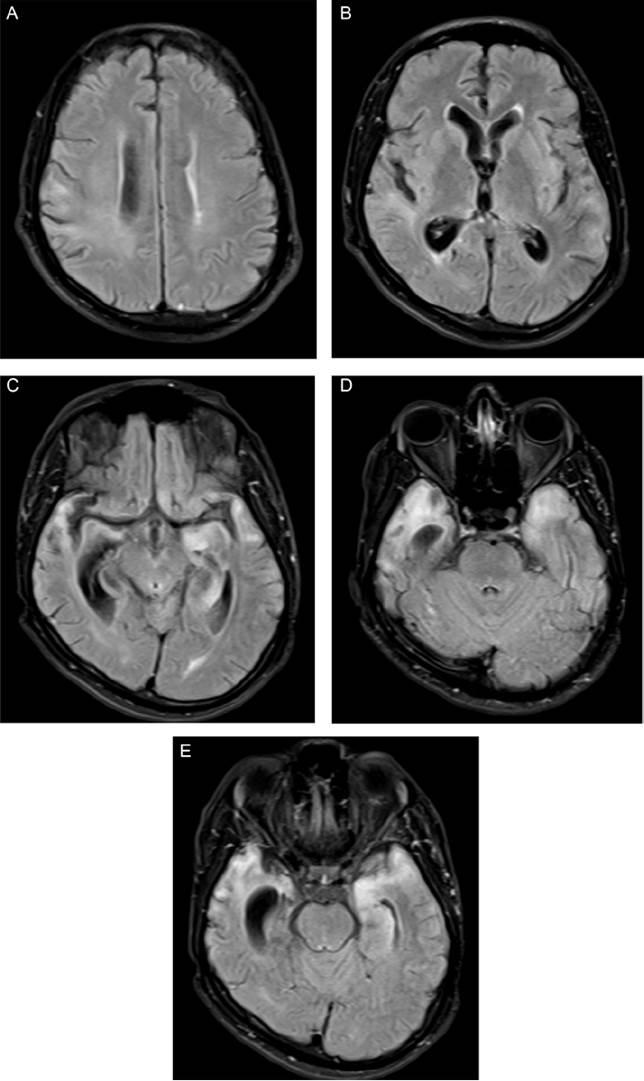

Imagenología

A pesar de que hasta 2 tercios de los pacientes con neurosífilis tienen reportes normales en la tomografía computarizada, la resonancia magnética ola angiografía20, la neurosífilis puede tener una amplia variedad de presentaciones en los diferentes tipos de ayudas imagenológicas cerebrales21,23.

Los cambios imagenológicos que tienen que ver con la neurosífilis son particularmente variables, pero por su mayor frecuencia destacan la atrofia encefálica leve-moderada, los infartos cerebrales típicamente lacunares o en el territorio de la arteria cerebral media, las lesiones inespecíficas en la sustancia blanca y la prominencia periventricular de esta, la hidrocefalia, las gomas cerebrales, la esclerosis mesial-temporal, el realce leptomeníngeo, los granulomas leptomeníngeos, la periostitis orbitaria gomatosa y la periostitis que afecta a la cápsula óptica20,23.

No obstante, algunos autores han planteado la posibilidad de que muchos de los hallazgos anteriormente mencionados pueden deberse a posibles coinfecciones, como se puede observar en pacientes con infección por el VIH, y siempre se debe tener en cuenta que existe una amplia gama de diagnósticos diferenciales una vez se encuentran lesiones de cualquier tipo en las imágenes cerebrales de ciertos grupos de pacientes22.

Asimismo, en pacientes sin infección por el VIH pueden darse diagnósticos como encefalitis por el virus del herpes simple, esclerosis mesial temporal, leucoaraiosis, hidrocefalia de presión normal y glioblastoma multiforme21.

En las figuras 2-3 se presentan imágenes correspondientes a casos tratados en el Hospital Psiquiátrico Universitario del Valle en los cuales se llegó al diagnóstico de neurosífilis.